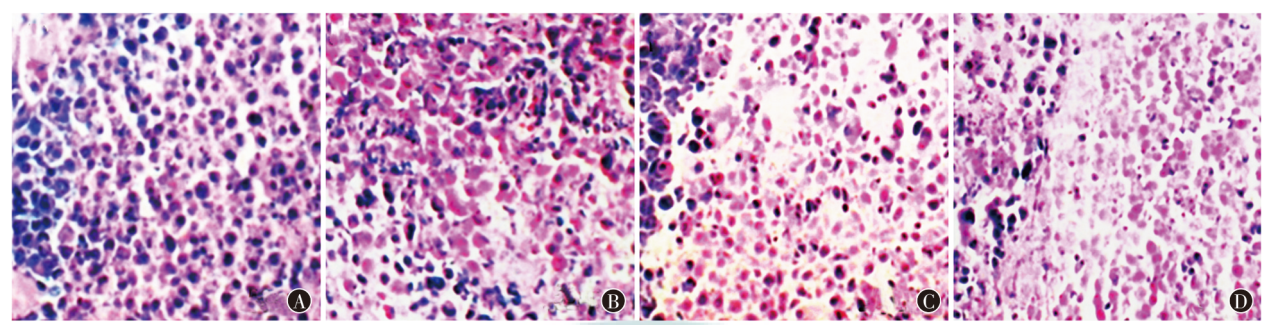

目的探究雷帕霉素动脉灌注联合负载131I-成纤维细胞活化蛋白(FAP)的葡聚糖微球介入栓塞治疗兔肝移植瘤的效果。方法选取50只雄性新西兰白兔,采用随机数字表法将40只白兔用于建模肝移植瘤,随机分为阴性对照组(基于动脉灌注同体积生理盐水,MO)组,雷帕霉素动脉灌注(RA)组,负载131I-FAP的葡聚糖微球介入栓塞治疗(IF)组,雷帕霉素动脉灌注联合负载131I-FAP的葡聚糖微球介入栓塞治疗(RI)组,每组10只;余10只未建模白兔为正常(基于动脉灌注同体积生理盐水,NO)组。采用HE染色检测肿瘤细胞病理形态,全自动生化分析仪检测肝功能,TUNEL法检测肿瘤细胞凋亡情况,蛋白质印迹法检测肝组织血管内皮生长因子(VEGF)、血管内皮生长因子受体(VEGFR)蛋白表达情况。结果MO组、RA组、IF组、RI组肿瘤质量分别为(20.33±2.39)、(14.62±1.23)、(14.34±1.22)、(8.28±0.84)g,肿瘤体积分别为(0.87±0.13)、(0.51±0.09)、(0.53±0.08)、(0.32±0.02)cm3,肿瘤坏死率分别为(21.11±2.14)%、(32.18±3.25)%、(32.29±3.28)%、(48.53±4.37)%,抑瘤率分别为(0.00±0.00)%、(24.66±2.47)%、(24.13±2.46)%、(45.55±4.51)%,差异均有统计学意义(F=316.40,P<0.001;F=159.50,P<0.001;F=356.10,P<0.001;F=571.30,P<0.001);与MO组比较,RA组、IF组、RI组差异均有统计学意义(均P<0.05);IF组与RI组比较,差异均有统计学意义(均P<0.05)。MO组肿瘤细胞呈浸润生长,核分裂像多见,未见明显坏死,可见大量炎性细胞浸润,RA组、IF组、RI组癌巢明显变小,肿瘤细胞出现肿胀、核固缩及大量坏死,炎性细胞浸润明显减轻,其中RI组改善最为明显。NO组、MO组、RA组、IF组、RI组白蛋白(ALB)水平分别为(40.55±4.38)、(17.34±1.02)、(22.65±2.18)、(22.37±2.17)、(29.01±2.83)g/L,丙氨酸氨基转移酶(ALT)水平分别为(19.68±1.34)、(92.17±9.24)、(78.71±7.39)、(78.35±7.40)、(50.30±5.12)U/L,天冬氨酸氨基转移酶(AST)水平分别为(74.27±7.48)、(182.21±20.23)、(165.78±16.05)、(165.26±16.09)、(102.33±11.11)U/L,总胆红素(TBIL)水平分别为(22.42±2.58)、(82.24±8.35)、(61.86±6.17)、(61.53±6.16)、(46.45±4.53)μmoL/L,差异均有统计学意义(F=105.90,P<0.001;F=189.00,P<0.001;F=99.57,P<0.001;F=142.10,P<0.001);与NO组比较,MO组、RA组、IF组、RI组差异均有统计学意义(均P<0.05);与MO组比较,RA组、IF组、RI组差异均有统计学意义(均P<0.05);IF组与RI组比较,差异均有统计学意义(均P<0.05)。MO组、RA组、IF组、RI组肿瘤细胞凋亡率分别为(9.01±1.23)%、(15.65±1.68)%、(15.72±1.69)%、(24.34±2.12)%,差异有统计学意义(F=135.30,P<0.001);与MO组比较,RA组、IF组、RI组差异均有统计学意义(均P<0.05);IF组与RI组比较,差异有统计学意义(P<0.05)。NO组、MO组、RA组、IF组、RI组VEGF表达水平分别为1.33±0.13、2.28±0.21、1.88±0.19、1.86±0.18、1.50±0.14,VEGFR表达水平分别为1.32±0.09、2.14±0.28、1.91±0.18、1.89±0.17、1.62±0.15,差异均有统计学意义(F=45.84,P<0.001;F=29.05,P<0.001);与NO组比较,MO组、RA组、IF组、RI组差异均有统计学意义(均P<0.05);与MO组比较,RA组、IF组、RI组差异均有统计学意义(均P<0.05);IF组与RI组比较,差异均有统计学意义(均P<0.05)。结论雷帕霉素动脉灌注联合负载131I-FAP的葡聚糖微球介入栓塞治疗兔肝移植瘤,可有效抑制肿瘤生长,提高肿瘤坏死率、抑瘤率以及凋亡能力,改善肝功能指标,对兔肝移植瘤有显著疗效。

ObjectiveTo investigate the efficacy of rapamycin arterial perfusion combined with131I-fibroblast activation protein (FAP) loaded dextran microspheres in the treatment of rabbits with liver transplantation tumor.MethodsFifty male New Zealand white rabbits were selected. Forty white rabbits were used to establish liver transplantation tumor models and were randomly divided into a negative control (based on arterial perfusion with the same volume of normal saline, MO) group, rapamycin arterial perfusion (RA) group,131I-FAP loaded dextran microspheres for interventional embolization therapy (IF) group, and rapamycin arterial perfusion combined with131I-FAP-loaded dextran microspheres interventional embolization therapy (RI) group by the random number table method, with 10 rabbits in each group. The remaining 10 unmodeled white rabbits were classified as the normal (based on arterial perfusion with the same volume of normal saline, NO) group. The pathological morphology of tumor tissues was detected by HE staining, liver function was detected by automatic biochemical analyzer, apoptosis of tumor cells was detected by TUNEL method, and the protein expression of vascular endothelial growth factor (VEGF) and vascular endothelial growth factor receptor (VEGFR) in liver tissues was detected by Western blotting.ResultsThe tumor mass of MO group, RA group, IF group and RI group was (20.33±2.39), (14.62±1.23), (14.34±1.22), (8.28±0.84) g, respectively. Tumor volumes were (0.87±0.13), (0.51±0.09), (0.53±0.08), (0.32±0.02) cm3, respectively. Tumor necrosis rates were (21.11±2.14)%, (32.18±3.25)%, (32.29±3.28)%, (48.53±4.37)%, respectively. Tumor suppression rates were (0.00±0.00)%, (24.66±2.47)%, (24.13±2.46)%, (45.55±4.51)%, respectively. There were statistically significant differences (F=316.40,P<0.001;F=159.50,P<0.001;F=356.10,P<0.001;F=571.30,P<0.001); there were statistically significant differences in RA, IF and RI groups compared with the MO group (allP<0.05); there were statistically significant differences between RI group and IF group (allP<0.05). Tumor cells of MO group showed infiltrating growth, with more mitotic images, no obvious necrosis, and a large number of inflammatory cell infiltration. Cancer nests in RA group, IF group and RI group became significantly smaller, tumor cells showed swelling, nuclear contraction and a large number of necrosis, and inflammatory cell infiltration was significantly reduced, among which the improvement was most obvious in RI group. The albumin (ALB) level of NO group, MO group, RA group, IF group and RI group was (40.55±4.38), (17.34±1.02), (22.65±2.18), (22.37±2.17), (29.01±2.83) g/L, respectively. The alanine aminotransferase (ALT) level was (19.68±1.34), (92.17±9.24), (78.71±7.39), (78.35±7.40), (50.30±5.12) U/L, respectively. The aspartate aminotransferase (AST) level was (74.27±7.48), (182.21±20.23), (165.78±16.05), (165.26±16.09), (102.33±11.11) U/L, respectively. The total bilirubin (TBIL) level was (22.42±2.58), (82.24±8.35), (61.86±6.17), (61.53±6.16), (46.45±4.53) μmoL/L, respectively. There were statistically significant differences (F=105.90,P<0.001;F=189.00,P<0.001;F=99.57,P<0.001;F=142.10,P<0.001); there were statistically significant differences in MO, RA, IF, RI groups compared with the NO group (allP<0.05); there were statistically significant differences in RA, IF, RI groups compared with the MO group (allP<0.05); there were statistically significant differences between IF group and RI group (allP<0.05). The apoptosis rates in MO group, RA group, IF group and RI group were (9.01±1.23)%, (15.65±1.68)%, (15.72±1.69)% and (24.34±2.12)%, respectively, and there was a statistically significant difference (F=135.30,P<0.001); there were statistically significant differences in RA, IF and RI groups compared with the MO group (allP<0.05); there was a statistically significant difference between RI group and IF group (P<0.05). VEGF expression level in NO group, MO group, RA group, IF group and RI group was 1.33±0.13, 2.28±0.21, 1.88±0.19, 1.86±0.18 and 1.50±0.14, respectively. VEGFR expression level was 1.32±0.09, 2.14±0.28, 1.91±0.18, 1.89±0.17, 1.62±0.15, respectively. There were statistically significant differences (F=45.84,P<0.001;F=29.05,P<0.001); there were statistically significant differences in MO, RA, IF, RI groups compared with the NO group (allP<0.05); there were statistically significant differences in RA, IF, RI groups compared with the MO group (allP<0.05); there were statistically significant differences between IF group and RI group (bothP<0.05).ConclusionsRapamycin arterial perfusion combined with131I-FAP-loaded dextran microspheres interventional embolization therapy in the treatment of rabbits with liver transplantation tumor can effectively inhibit tumor growth, enhance the tumor necrosis rate, tumor inhibition rate and apoptotic ability, improve liver function indicators, and has a significant therapeutic effect on rabbits with liver transplantation tumor.